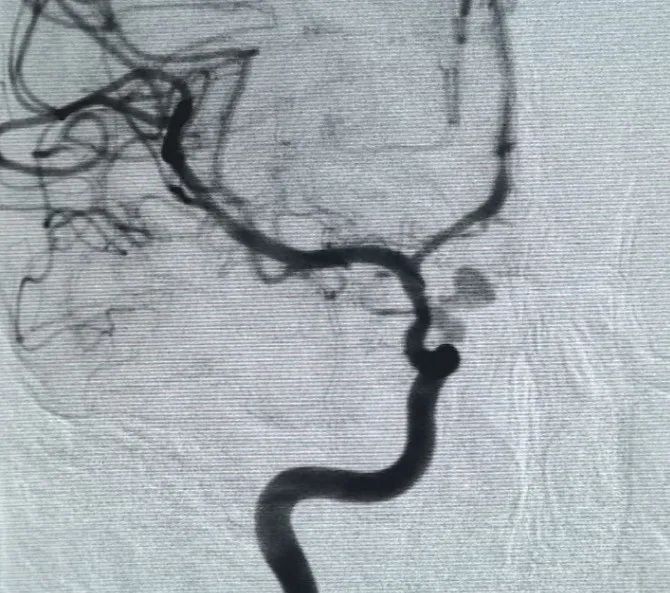

Perfiller®Cewka ekspansywna 3mm × 6 cm i Perfiller®Następnie umieszczono rozszerzalną cewkę o wymiarach 3mm × 2 cm, aby zakończyć okluzję szyjki. Następnie Nuva®Flow Diverter (TJED-D-5.0-16) został dostarczony i rozmieszczony w poprzek szyi tętniaka. Dalsza angiografia zarówno w widoku przednio-tylnym, jak i bocznym potwierdziła doskonałe pokrycie, dobre położenie ściany i wyraźną przezroczystość promieniową, z wyraźną stagnacją kontrastu.

Procedura została zakończona płynnie bez powikłań, a pacjent wyzdrowiał bez deficytów neurologicznych.